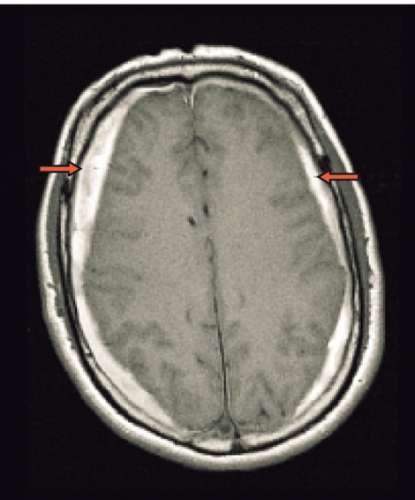

Spontan intrakraniell hypotension är sannolikt ett underdiagnostiserat tillstånd som man bör tänka på hos patienter med nytillkommen daglig huvudvärk, särskilt om den förvärras i stående (Fakta 1). För att ställa diagnos gäller att likvortrycket ska vara lågt, helst <6 cm H2O i liggande, och MRT med kontrast (helst före lumbalpunktion) ska visa generell dural uppladdning (s k pakymeningit) och karakteristiska förändringar av hjärnstammen (Fakta 2) [1, 2]. Initial behandling är symtomlindring med sängläge och gradvis mobilisering. Den kompletteras ofta med rikligt vätskeintag och koffein, antingen i tablettform eller som dropp. Om detta inte ger effekt är epidural injektion av autologt blod (»blood patch«) nästa steg, som ger snabb effekt hos de flesta patienter men som kan behöva upprepas [3]. Vid terapiresistens övervägs utvidgad neuroradiologisk utredning för att lokalisera likvorläckagestället. Då finns möjlighet att upprepa blodinjektionen över själva läckagestället. Om det inte hjälper kan kirurgiskt ingrepp diskuteras [2]. Etiologi och patogenes År 1938 beskrev den tyske läkaren Georg Schaltenbrand det tillstånd som kom att kallas spontan intrakraniell hypotension [4, 5]. Då trodde man att orsaken var minskad produktion av likvor från plexus choroideus eller ökad absorption, men bevis saknades. I dag vet man att tillståndet beror på likvorläckage, sannolikt på grund av en defekt i dura mater. Vid utredning har man kunnat påvisa spinala epidurala cystor (divertiklar) som bedömts ha rupturerat spontant eller vid en plötslig tryckstegring i likvorrummet. Det är också känt att osteofyter och diskbråck kan orsaka läckage genom att erodera duran [6, 7]. I dessa fall kan operation bli nödvändig [8]. Vid kirurgi kan man se många olika durala avvikelser, såsom rifter och meningeala cystor [9-11]. Spontan intrakraniell hypotension uppkommer förmodligen i vissa fall av en kombination av lindrigt trauma och underliggande spinal patologi [2, 12]. Enligt litteraturen har upp till en tredjedel av patienterna en oupptäckt bindvävssjukdom. Många har morfologiska tecken på bindvävssjukdom, såsom lång och smal kroppsbyggnad, spindelfingrar och överrörlighet i lederna [13, 14]. I de flesta fall är dock bindvävssjukdomen ospecifik, och endast i ca 5 procent av fallen har en specifik diagnos kunnat ställas, såsom Marfans syndrom eller Ehlers–Danlos syndrom typ II [13, 15-17]. Familjär spontan intrakraniell hypotension har även beskrivits [18]. Det är viktigt att veta att ett normalt spinalt öppningstryck (7–20 cm H2O) inte utesluter diagnosen [12]. Hos en patient med normalt tryck är det symtomen och tecknen på MRT som ger diagnosen. Många menar att förlust av likvor är den verkliga orsaken till syndromet och att hypotensionen är en följd av hypovolemin [19]. Likvorhypovolemisyndrom (CSF hypovolemia syndrome) har därför föreslagits som ett nytt namn på tillståndet [19]. Läckagestället är nästan alltid beläget i cervikotorakala delen, ofta i cervikotorakala övergången [12]. I praktiken kan det vara svårt att fastställa ett exakt läckageställe. Ofta samlas vätska bakom durasäcken i höjd med kotkropparna C1–C2 [20]. Denna vätskeansamling är dock inte ett säkert tecken på läckage från detta område. Det kan vara en falsk lokalisation. Sannolikt kommer läckaget från en annan nivå, och vätskan förflyttas uppåt till övre halsryggen [20]. Ibland kan man se multipla läckageställen samtidigt [21]. Epidemiologi Spontan intrakraniell hypotension har länge ansetts vara mycket sällsynt. Men kanske är tillståndet inte så ovanligt. Inga säkra siffror från samhällsbaserade studier finns tillgängliga för att beräkna incidensen och prevalensen. I en studie av radiologiska undersökningar på en akutavdelning diagnostiserades sjukdomen ungefär hälften så ofta som spontan subaraknoidalblödning – med en uppskattad årlig incidens på 5/100 000 [22]. På ett sjukhus i Rom diagnostiserades 82 patienter under en 18-årsperiod, 1992–2009, av vilka 40 behandlades konservativt med sängläge och 42 med lumbal epidural injektion av autologt blod [3]. På vår klinik har vi haft 10–15 patienter med detta tillstånd de senaste fyra åren. Den högsta incidensen av spontan intrakraniell hyptension ses vid vid ca 40 års ålder, men fall har beskrivits hos personer mellan 3 och 86 års ålder. Sjukdomen tenderar att drabba kvinnor något oftare än män (kvot ca 1,5:1) [2]. Kliniska symtom Den vanligaste kliniska manifestationen av spontan intrakraniell hypotension är ortostatisk huvudvärk, som förvärras gradvis med maximal intensitet efter flera minuter till timmar. Det händer att huvudvärken debuterar plötsligt. Man misstänker då ofta subaraknoidalblödning, och patienten utreds av denna anledning [23]. De allra flesta patienter kan minnas dagen då huvudvärken började, om än inte den exakta tidpunkten. Huvudvärken brukar beskrivas som diffus, pulserande eller icke-pulserande och är vanligen lokaliserad till nackregionen men kan också vara frontotemporal. Huvudvärken behöver inte vara symmetrisk men är sällan helt ensidig. Hur allvarlig huvudvärken är varierar, och det är troligt att en del lindriga fall förblir oupptäckta och att läkning sker spontant. En ledtråd till diagnosen kan vara om patienten beskriver en dragningskänsla från huvudet ner till nacken. Ytterligare ledtrådar är om patienten föredrar att ligga ned på undersökningsbritsen eller har en kudde med sig [2]. Även om ortostatisk huvudvärk är det kliniska kännetecknet, vilket återspeglas i alla diagnostiska kriterier, är det välkänt att den ortostatiska komponenten ofta blir mindre framträdande eller försvinner med tiden. Dessutom har patienter vars huvudvärk från början har saknat ortostatisk komponent beskrivits [24, 25]. Den exakta orsaken till huvudvärken är inte känd, men man antar att det är förlusten av likvor som orsakar neddragningen av hjärnan med sekundär dragning av smärtkänsliga intrakraniella strukturer [12]. En alternativ förklaring är att det sker en kompensatorisk dilatation av smärtkänsliga intrakraniella venösa strukturer. Förutom huvudvärk har många andra symtom rapporterats. De vanligaste, som förekommer i mer än hälften av fallen, är nacksmärta eller nackstelhet, illamående och kräkningar. Upp till hälften av patienterna beskriver lockkänsla eller tinnitus, och ca 10 procent uppvisar kranialnervspåverkan (vanligtvis abducenspares) med dubbelseende [12]. Abducensnerven har en lång och komplicerad väg intrakraniellt och är därför särskilt utsatt. MRT-undersökning av hjärnan MRT har revolutionerat inte bara erkännandet av sjukdomen utan också förståelsen av den [2]. MRT har i hög grad underlättat möjligheten att komma fram till en säker diagnos utan att behöva använda ingrepp som lumbalpunktion. MRT är förmodligen den viktigaste faktorn bakom det ständigt ökade antalet patienter med spontan intrakraniell hypotension sedan början av 1990-talet [2]. Det typiska fyndet vid cerebral MRT är generell pakymeningit (Figur 1). Pakymeningit i samband med spontan intrakraniell hypotension beskrevs första gången år 1991 av Mokri et al [26]. Det är dock viktigt att veta att upp till 20 procent av patienterna med spontan intrakraniell hypotension inte har någon tydlig pakymeningit [27]. Man tror att den meningeala förtjockningen beror på dural vasodilatation. Grunden för detta är Monroe–Kellie-doktrinen, enligt vilken summan av intrakraniellt blod, likvor och hjärnvävnad ska vara konstant i ett intakt kranium. Det innebär att minskningen av likvor leder till kompensatorisk vasodilatation [12, 19]. De flesta av förändringarna som ses vid MRT kan förklaras av dessa kompensatoriska mekanismer med pakymeningeal uppladdning, vidgning av venösa strukturer och hypofysförstoring. »Sagging«, eller neddragning, av hjärnan är ett typiskt radiologiskt fynd vid spontan intrakraniell hypotension (Figur 2). Det ses tydligast på en sagittal MRT-bild med neddragning av hjärnstam och lillhjärnstonsiller genom foramen magnum som vid Chiari-missbildning typ 1 (Figur 2). Subdural vätska (effusioner och hematom) förekommer hos ca 50 procent av patienterna (Figur 3). Oftast är dessa vätskeansamlingar tunna, bilaterala och lokaliserade till ovanför storhjärnshemisfärerna, orsakade av bristningar i bryggvener, utan någon märkbar expansiv effekt. Vätskeansamling ses ibland i bakre skallgropen, särskilt över lillhjärnshemsifärerna eller bakom clivus. Dessa vätskeansamlingar brukar försvinna när behandling sätts in mot det underliggande spinala likvorläckaget 28]. Om kirurgin riktas endast mot vätskeansamlingarna utan att läckaget behandlas är risken för recidiv ganska stor. Hypofysär hyperemi med förstoring av körteln är ett annat radiologiskt tecken på spontan intrakraniell hypotension [29]. Förstoringen kan bli ganska anslående och kan likna en hypofystumör. Det finns många tillstånd som radiologiskt kan likna spontan intrakraniell hypotension. Den förtjockade kontrastladdade duran kan misstolkas som ett kroniskt subduralhematom, men i dessa fall ses i regel ett vätskespatium mellan uppladdningarna. Idiopatisk hypertrofisk pakymeningit ger oftare fokal, dural förtjockning och inte den jämna, kontinuerliga uppladdningen som vid hypotensionssyndromet. Framför allt gäller detta vid granulomatös meningit och meningeal karcinomatos, vilka också oftare drabbar de mjuka hinnorna än den hårda hjärnhinnan. Meningealt lymfom och durala metastaser liksom meningiom med »dural svans« har ofta associerade skelettförändringar. Vid alla ovan nämnda tillstånd saknas dessutom den typiska bilden av neddragen hjärna. Spinal MRT Spinal MRT kan visa områden med extradural vätskeansamling (särskilt vid C1–C2) (Figur 4 och 5), meningeala divertiklar, dilatation av epidurala vener, dural uppladdning och komprimerad durasäck [30-32]. DT-myelografi Lumbalpunktion med injektion av jodkontrast följt av DT-myelografi med tunna snitt och reformateringar av hela ryggraden har visat sig vara en bra metod för att definiera läckagets exakta lokalisering och omfattning. DT-myelografi har visat sig ha störst känslighet vad gäller att lokalisera läckagestället [32]. Icke-invasiva undersökningar som spinal MRT rekommenderas dock i första hand [33]. Myelografi med intratekal administration av gadolinium följt av MRT är ett alternativ som ibland används utomlands [34] men är ännu inte godkänd på indikationen spontan intrakraniell hypotension i Sverige. Lumbalpunktion Vanligtvis är öppningstrycket <6 cm H2O, och det kan vara omätbart. Det är dock väl dokumenterat att en del patienter med spinalt likvorläckage kan ha ett normalt öppningstryck [33]. Den förhöjda halten av protein och/eller förekomst av xantokromi beror troligen på ökad permeabilitet i dilaterade meningeala blodkärl. Behandling Även om detaljerade uppgifter saknas sker sannolikt spontanläkning i de flesta fall av spontan intrakraniell hypotension. Symtomlindring med sängläge och gradvis mobilisering är en väldokumenterad behandling [12]. Koffein och teofyllin har också visat viss effekt [12]. Om sängläge inte hjälper är den vanliga behandlingen injektion av autologt blod (10–30 ml) epiduralt i ländryggen [35]. Om behandlingen misslyckas kan den upprepas en till två gånger, och man kan då spruta in större mängder blod, upp till 40 ml. Med tanke på den potentiellt stora volymen blod som injiceras rekommenderas några dagars mellanrum vid upprepad behandling. Volymen blod som kan injiceras begränsas huvudsakligen av ryggsmärta eller radikulopati. Det rekommenderas att patienten bibehåller planläge efter injektionen för att minska likvorflödet genom duradefekten och därmed hjälpa till att stänga hålet. Det har diskuterats om injektion av autologt blod verkligen hjälper när läckagestället är på cervikotorakal nivå. En del rapporter finns som visar att behandlingen är effektiv [36, 37]. I den tidigare nämnda studien från Rom [3] behandlades 42 patienter med spontan intrakraniell hypotension på dettta sätt med stor framgång, trots att läckaget i de flesta fall var på cervikotorakal nivå. 38 patienter (90 procent) blev återställda efter ett ingrepp, 2 patienter (5 procent) efter två ingrepp och 2 patienter (5 procent) efter tre ingrepp. Författarna rekommenderar dock konservativ behandling under tio dagar innan blodinjektion ges. Romgruppen lät patienterna ligga i Trendelenburgläge 1 timme före och 24 timmar efter ingreppet. Intressant nog behandlade de patienterna med acetazolamid, 250 mg i tablettform, 18 och 6 timmar före ingreppet. Acetazolamid är en karbanhydrashämmare som minskar produktionen av likvor. Romgruppen för ett resonemang om huruvida premedicineringen och långvarigt Trendelenburgläge kan minska likvorflödet genom duradefekten och därmed hjälpa till att stänga hålet. Dessutom kan premedicineringen minska risken för återuppkomst av tillståndet [38]. Om den lumbala blodinjektionen inte hjälper kan man försöka injicera blod eller fibrinlim (Tissel) direkt över läckagestället. Dessa behandlingar kräver att läckagestället är känt. Placering av fibrinlim ger förmodligen den bästa symtomlindrande effekten [39]. När konservativ behandling och blod eller fibrinlim inte ger effekt kan kirurgi vara ett alternativ [8, 12]. Kirurgi innebär bl a ligering av meningeala divertiklar, packning med spongostan, fibrinlim eller gelskum i epidurala rummet, suturering av durarifter samt resektion av osteofyter och diskbråck. Prognos Långtidsuppföljningarna av naturalförlopp och behandlingsresultat är knapphändiga, men spontan intrakraniell hypotension tros återkomma hos ca 10 procent, oavsett behandling. Patienter med en radiologisk bild som är typisk för spontan intrakraniell hypotension och med känt läckageställe har utmärkt prognos, medan personer med normal MRT-undersökning och diffus spinalt likvorläckage på flera nivåer tycks ha sämre prognos [2]. Vissa patienter har kvarstående symtom efter behandling trots dokumenterat upphävt likvorläckage. Dessa patienter är svåra att behandla, och det är oklart om de har förändrad likvordynamik eller kanske små rester av likvorläckage som inte syns på röntgenbilder. * Potentiella bindningar eller jävsförhållanden: Inga uppgivna.